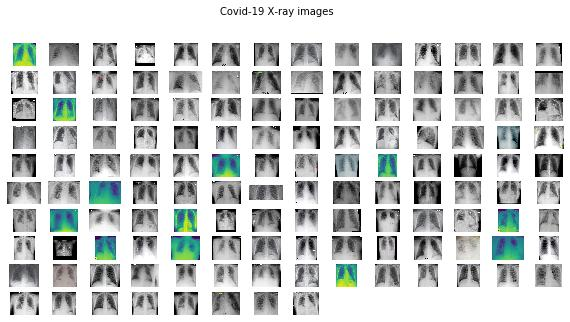

绘制数据集

由于文件夹中的图像数量不多,因此可以对其进行可视化检查,为此使用 plots_from_files():

def plots_from_files(imspaths, figsize=(10, 5), rows=1, titles=None, maintitle=None): """Plot the images in a grid""" f = plt.figure(figsize=figsize) if maintitle is not None: plt.suptitle(maintitle, fontsize=10) for i in range(len(imspaths)): sp = f.add_subplot(rows, ceildiv(len(imspaths), rows), i + 1) sp.axis('Off') if titles is not None: sp.set_title(titles[i], fontsize=16) img = plt.imread(imspaths[i]) plt.imshow(img)def ceildiv(a, b): return -(-a // b)

然后,定义将在训练中使用的数据集的路径和带有要查看的图像名称的列表:

dataset_path = '../10_dataset'normal_images = list(paths.list_images(f"{dataset_path}/normal"))covid_images = list(paths.list_images(f"{dataset_path}/covid"))

通过调用可视化支持函数,可以显示以下图像:

plots_from_files(covid_images, rows=10, maintitle="Covid-19 X-ray images")

plots_from_files(normal_images, rows=10, maintitle="Normal X-ray images")

图像看起来不错。